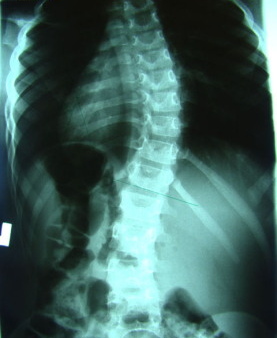

Szanowni Państwo, w trosce o zdrowie naszych mieszkańców informujemy, że dzięki uprzejmości kardy specjalistów ze Śląskiego Uniwersytetu Medycznego w Katowicach, dla dzieci z klas pierwszych uczęszczających do szkół w naszej gminie, zostaną zorganizowane bezpłatne badania skoliozy.

Badania te odbędą się w czerwcu tego roku i wymagać będą zgody prawnych opiekunów dzieci. Serdecznie prosimy o rozważne i przychylne włączenie się w inicjatywę. Wcześnie wykryte zwyrodnienia kręgosłupa w wielu przypadkach mogą zostać znacząco skorygowane, a co za tym idzie umożliwić Państwa dzieciom zachowanie zdrowia w przyszłości! Nie odbierajmy dzieciom możliwości funkcjonowania bez ograniczeń! Skorzystajmy z podarowanej nam szansy!